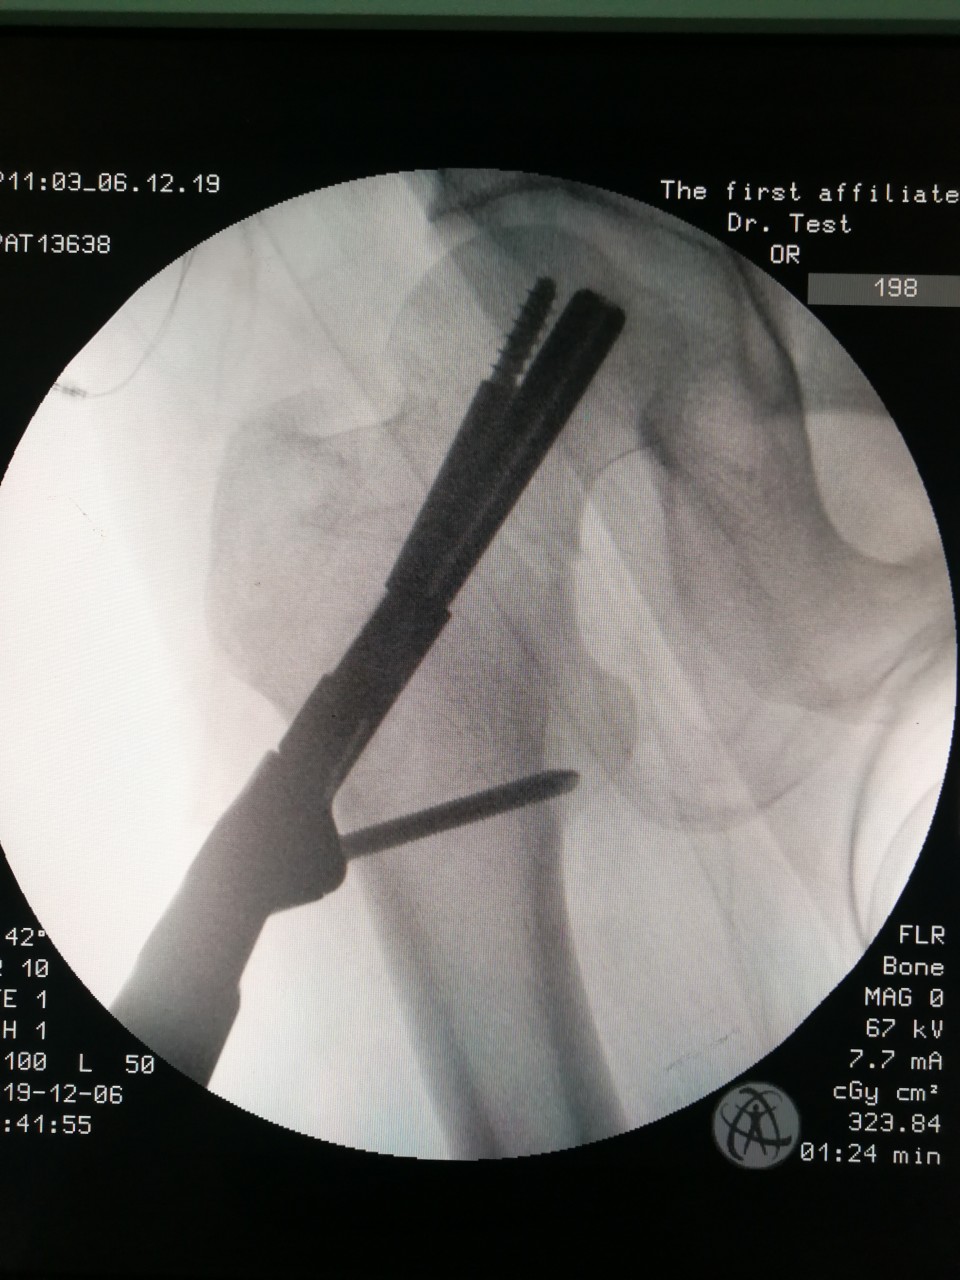

近日,创伤骨科7东运用新型的手术及内固定方式完成了一例股骨颈骨折的治疗。患者50岁,男性,因外伤致股骨颈骨折入住我院创伤骨科,诊断为股骨颈骨折(Garden III型),经创伤骨科王刚副主任医师团队术前讨论后,决定采用最新的“股骨颈动力交叉钉系统(FNS)”给患者进行微创手术。手术顺利,术后第3日患者出院。

据悉,股骨颈骨折常见于中老年患者,其临床治疗中存在骨折不愈合和缺血性坏死两个主要难题,主流的内固定方式有两种,一是动力髋系统,其力学稳定但是创伤大,手术时间长,操作复杂;二是空心螺钉,属于微创治疗,但由于力学稳定性不足,术后需要长时间卧床和拄拐,康复时间很长。“股骨颈动力交叉钉系统(FNS)”是最新的股骨颈骨折微创治疗解决方案,其结合了空心螺钉微创和动力髋系统力学稳定的优势,操作简便微创治疗的同时,又能提供较好的力学稳定性。

此次王刚副主任医师团队为该患者选择FNS作为治疗方案,患者恢复快,可早期下地行走活动,缩短住院时间及康复时间,符合快速康复ERAS理念,这是FNS系统在我院的首次应用,今后创伤骨科会将此项技术应用到更多合适的患者中,为股骨颈骨折患者的快速康复提供最佳的治疗方案。